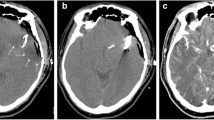

A clear depiction and delineation of small, peripheral vessels in a patient example is given in Fig. 4, and the remarkable superiority of UHR-CT in the visualization of peripheral and small vessel branches and their delineation is demonstrated in volume rendering (Fig. 5). The improved image quality of the vertebrobasilar area is also substantial: VA: UHR-CTA = 4 (4–4) vs NR-CTA = 3 (3–4) PICA: UHR-CTA = 4 (3–4) vs NR-CTA = 3 (2–3); AICA: UHR-CTA = 4 (3–4) vs NR-CTA = 3 (2–3). The apparent differences in delineation of peripheral cerebral vessels are illustrated in Fig. 5.

Two exemplary patients with the same clinical characteristics. a Maximum intensity projection with a slice thickness of 17.5 mm calculated on an UHR-CTA data set in sagittal view. b Maximum intensity projection with a slice thickness of 17.5 mm calculated on an NR-CTA data set in sagittal view. In contrast to NR-CTA, the significantly improved visualization of the small vessel branches in UHR-CTA can be considerably emphasized